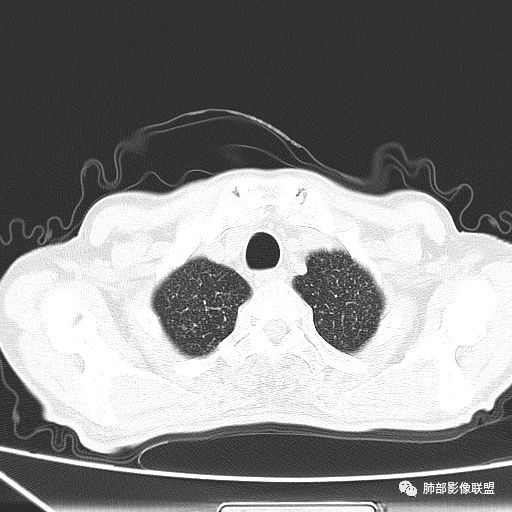

2019年9月12日CT(外院片,手机拍摄)